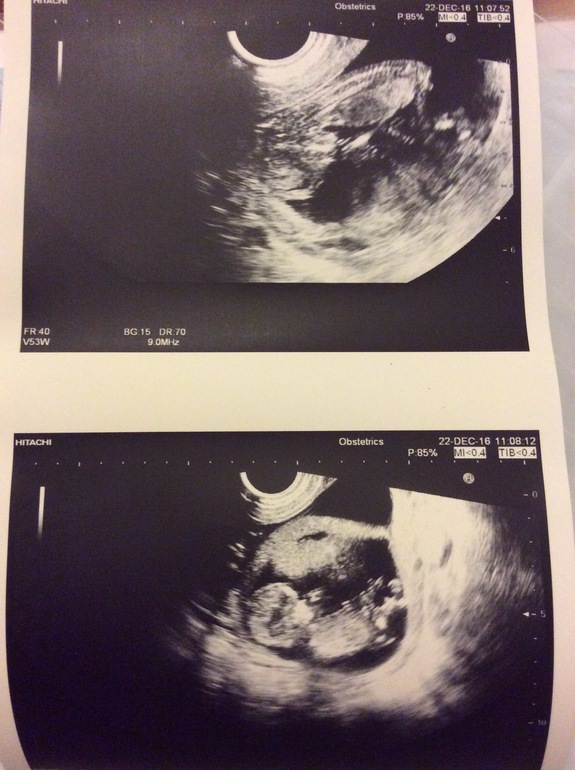

Наше УЗИ 12 недели:)

Вот так выглядят пупсики. Сказали,что малыши разнояйцевый и у каждого своя плацента. Они растут каждый по себе не мешая друг другу. Рост сейчас их составляет 66 мм обоих. Ноже в норме все. Токсикоза которого не было,так и не появился( только отрыжки замучали). Кстати прикупила себе подушку для беременных бумеранг,эта такая удобная штука,что я не слезаю с неё.